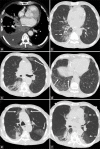

Pembrolizumab-related pneumonitis in a patient with COVID-19 infection